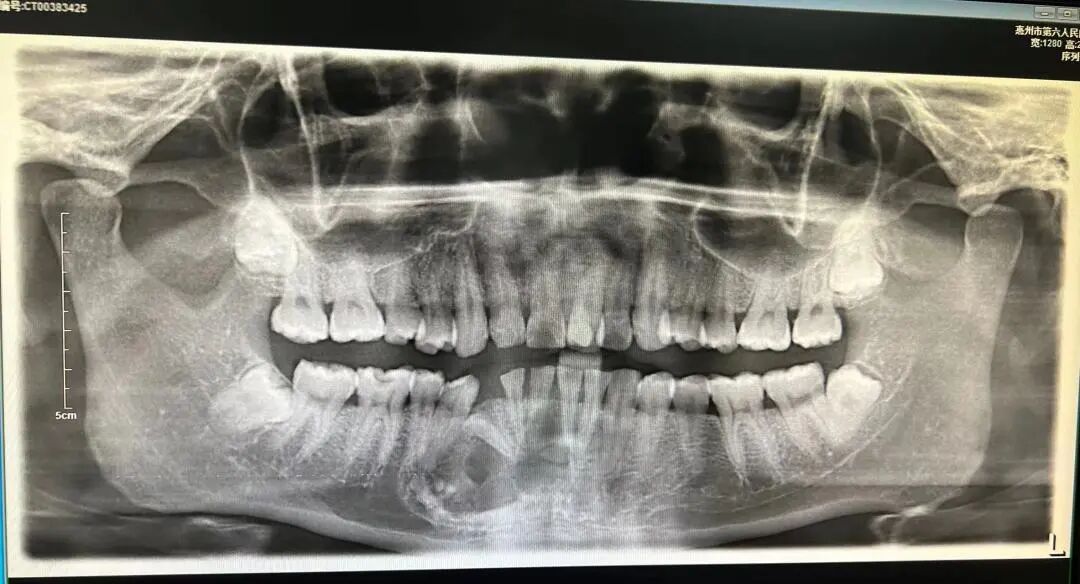

▲術前口腔全景片

成(chéng)牙骨質細胞瘤(Cementoblastoma)又名良性成(chéng)牙骨質細胞瘤(Benign cementoblastoma),真性牙骨質瘤(True cementoma),由不規則形或圓形團塊的牙骨質樣(yàng)組織組成(chéng),與牙根相融合,常使牙根吸收。

腫瘤多發(fā)生于磨牙或前磨牙的根尖部,與牙根融合;下颌比上颌多見,下颌第一磨牙區爲好(hǎo)發(fā)部位。腫瘤生長(cháng)緩慢,一般無自覺症狀,如腫瘤增大時(shí),可使牙槽骨膨脹,有時(shí)伴有神經(jīng)症狀。